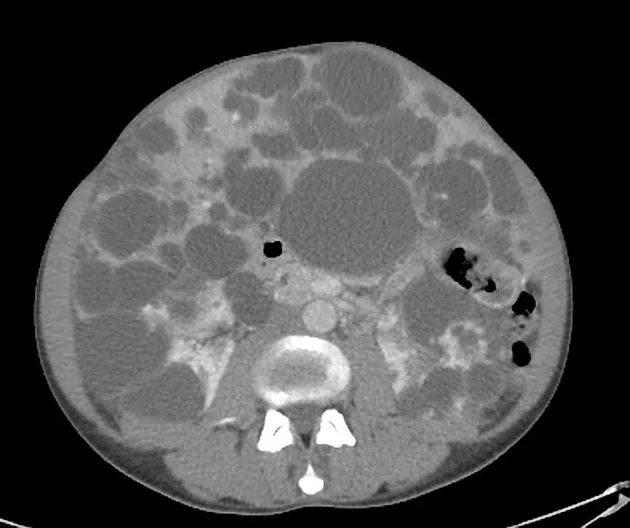

Injúria Renal Aguda (revisão Lancet 2025)